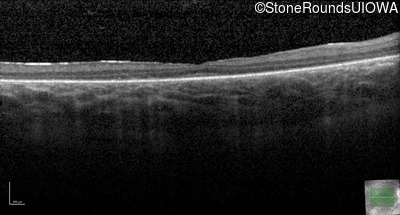

Optical Coherence Tomography - Right - 20/80 -1

Exemplar / OCT Stack